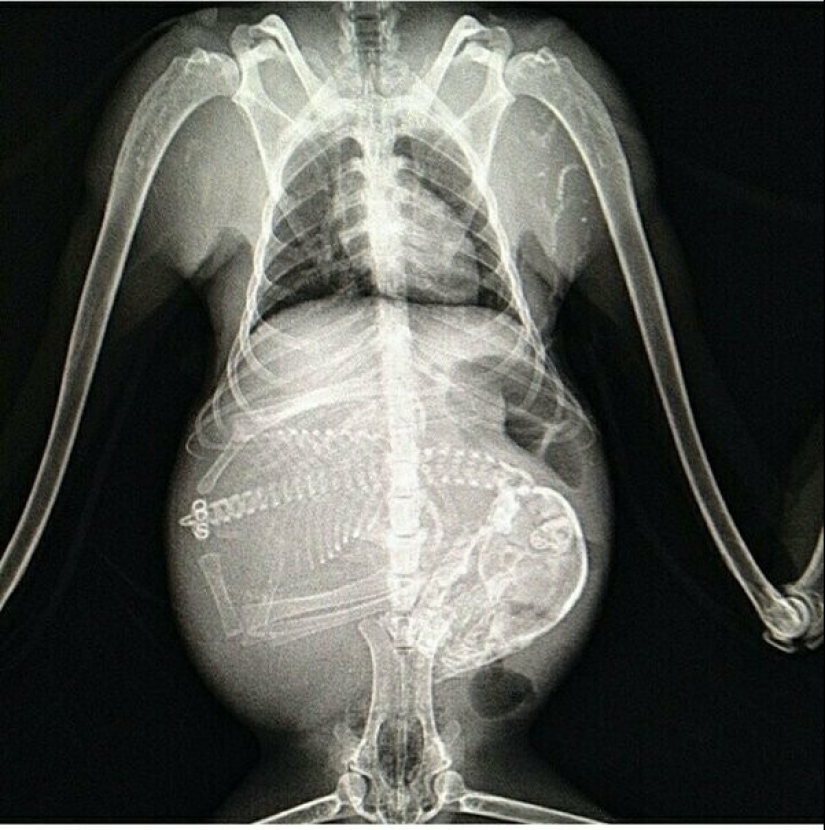

gata preñada